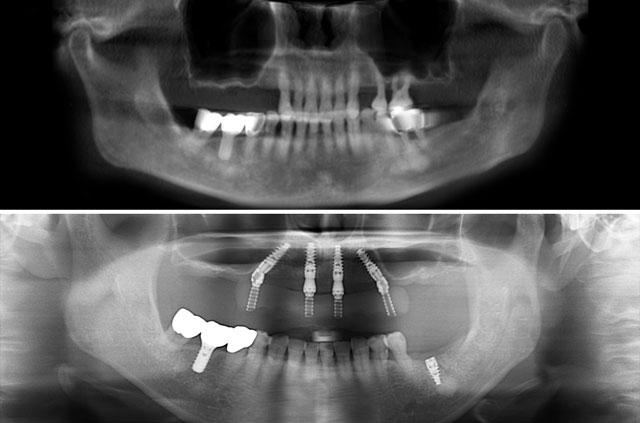

All-on-4 is a revolutionary dental implant technique that uses just four strategically placed implants to support a full arch of replacement teeth. The posterior implants are angled at 30-45 degrees to maximize bone contact and avoid anatomical structures like the maxillary sinus or inferior alveolar nerve. This innovative approach allows for immediate loading with a temporary prosthesis, providing same-day teeth and eliminating the need for lengthy healing periods between procedures.